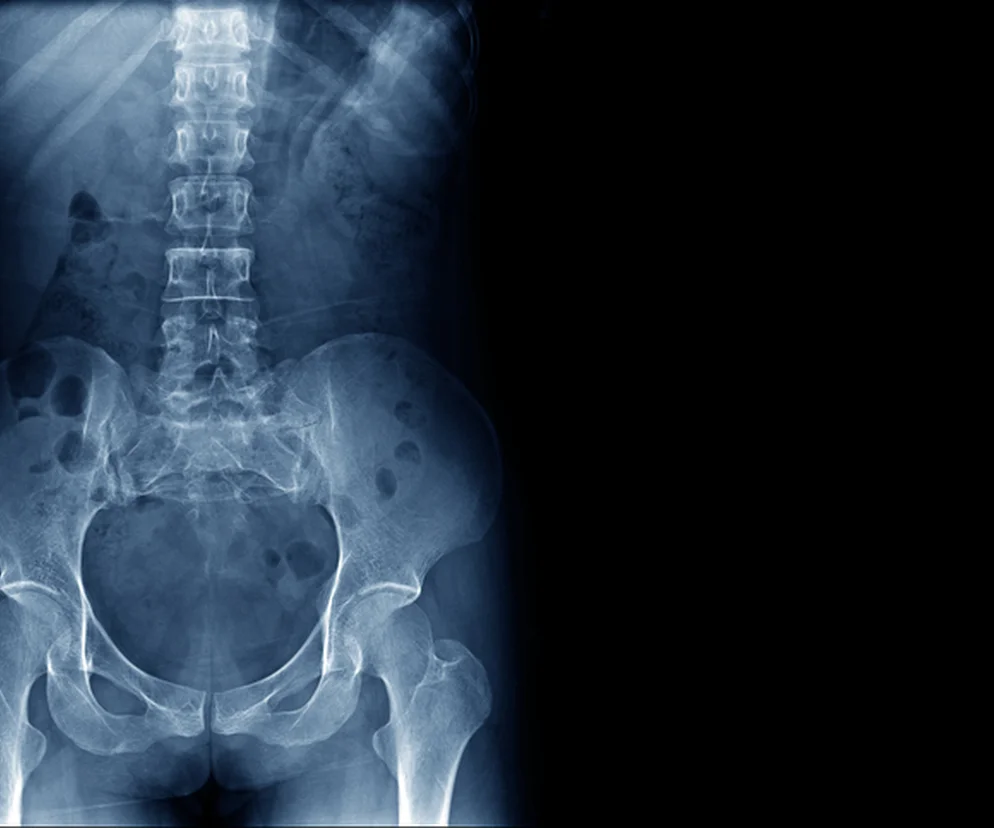

Spojenie łonowe (łac. symphysis pubica) jest chrząstkozrostem, czyli połączeniem kości za pomocą chrząstki i stanowi element strukturalny miednicy. Spojenie łonowe jest zlokalizowane zarówno u kobiet, jak i mężczyzn w dolnej części brzucha w okolicy narządów płciowych. U zdrowych dorosłych można je przesunąć o około 2 mm i obrócić o 1 stopień. Jednak warto zaznaczyć, że u kobiet w ciąży spojenie łonowe może być bardziej ruchome. Główną funkcją spojenia łonowego jest łączenie kości łonowych miednicy oraz ochrona narządów wewnętrznych przed urazami np. macicy u kobiet. Oprócz tego pomaga w amortyzowaniu wstrząsów w trakcie ruchu.

Spojenie łonowe – budowa

Spojenie łonowe składa się z:

• dwóch kości łonowych pokrytych chrząstką szklistą (łac. facies symphysialis)

• krążka międzyłonowego (łac. discus interpubicus), który jest zbudowany z chrząstki włóknistej i znajduje się pomiędzy kośćmi łonowymi; krążek międzyłonowy może posiadać niewielką jamkę

Warto zaznaczyć, że spojenie łonowe ma trochę odmienną budowę u każdej z płci. U mężczyzn jest ono wysokie a kąt podłonowy pomiędzy dolnymi kości łonowych wynosi 50-80 stopni. Natomiast u kobiet spojenie łonowe jest niskie a kąt podłonowy wynosi 90-110 stopni.